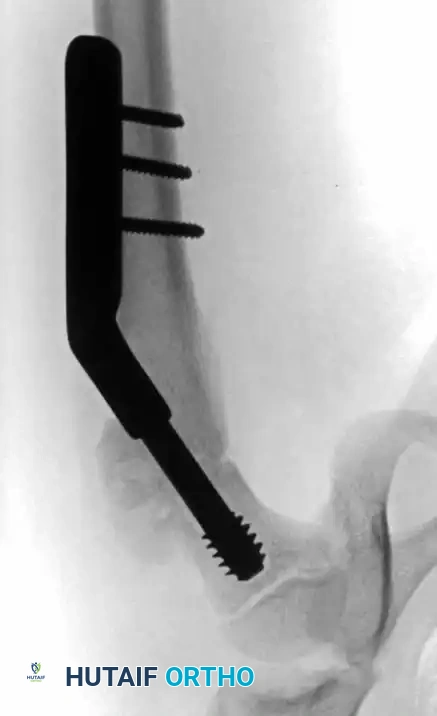

- Technique: Closed reduction and internal fixation using a pediatric locking proximal femoral plate or a dynamic hip screw.

Fig. 19: Intertrochanteric fracture managed with a pediatric proximal femoral locking plate.

Fig. 20: Lateral view of plate fixation ensuring no hardware encroaches on the trochanteric apophysis.